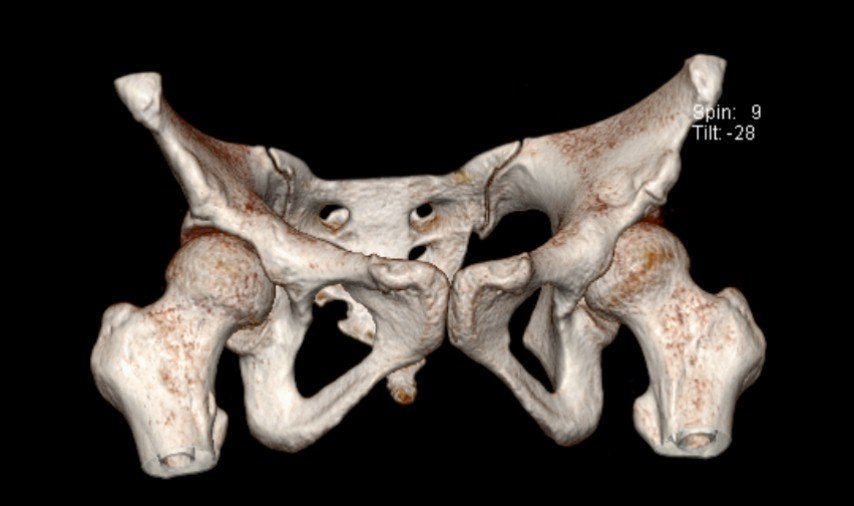

术前检查 X线 CT和单髋MRI

X线、CT检查能排除髋关节退变、发育不良、骨关节炎、髋关节撞击等骨性异常结构,但不能很好显示软组织病变,因此不能诊断髋臼盂唇损伤。MR检查具有较好的软组织对比性,分辨率较高,可多方位和多序列的成像,可以直接显示髋臼盂唇的形态和信号。MR检查又有MRI(MR Imaging)和MRA(MR Arthrography)之分,后者又可分为直接关节造影(Direct MR Arthrography )和间接关节造影(Idirect MR Arthrography)。